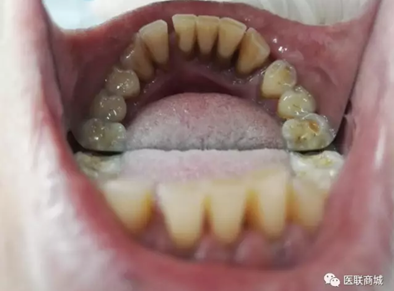

處置:首先進行常規(guī)的牙周刮治,治療效果已經(jīng)很明顯,見圖片。